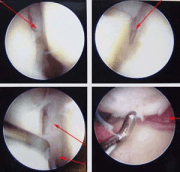

Arthro means joint and scope means camera. Athroscopy is a minimally invasive surgery that uses very small incisions that allow a camera and instruments to be put into the joint. Each incision is approximately 3mm and often surgery can be done making 3 to 4 such small incisions.

Wrist arthroscopy is a great tool. It can be used for chronic pain where the diagnosis is uncertain. This is called diagnostic arthroscopy. It can also be used to treat many conditions that otherwise would require a much larger open incision. This can include synovectomy (cleaning out inflammation), repair of ligaments (especially the ligament on the small finger side of the wrist, the TFCC) and even some fractures of the wrist.

Because the incisions are small, there is much less pain than a larger surgery and often the recovery can be quick. In addition, the arthroscope allows access deep in the wrist and essentially in all areas of the wrist and so with a small incision, you can see up close and be thorough.